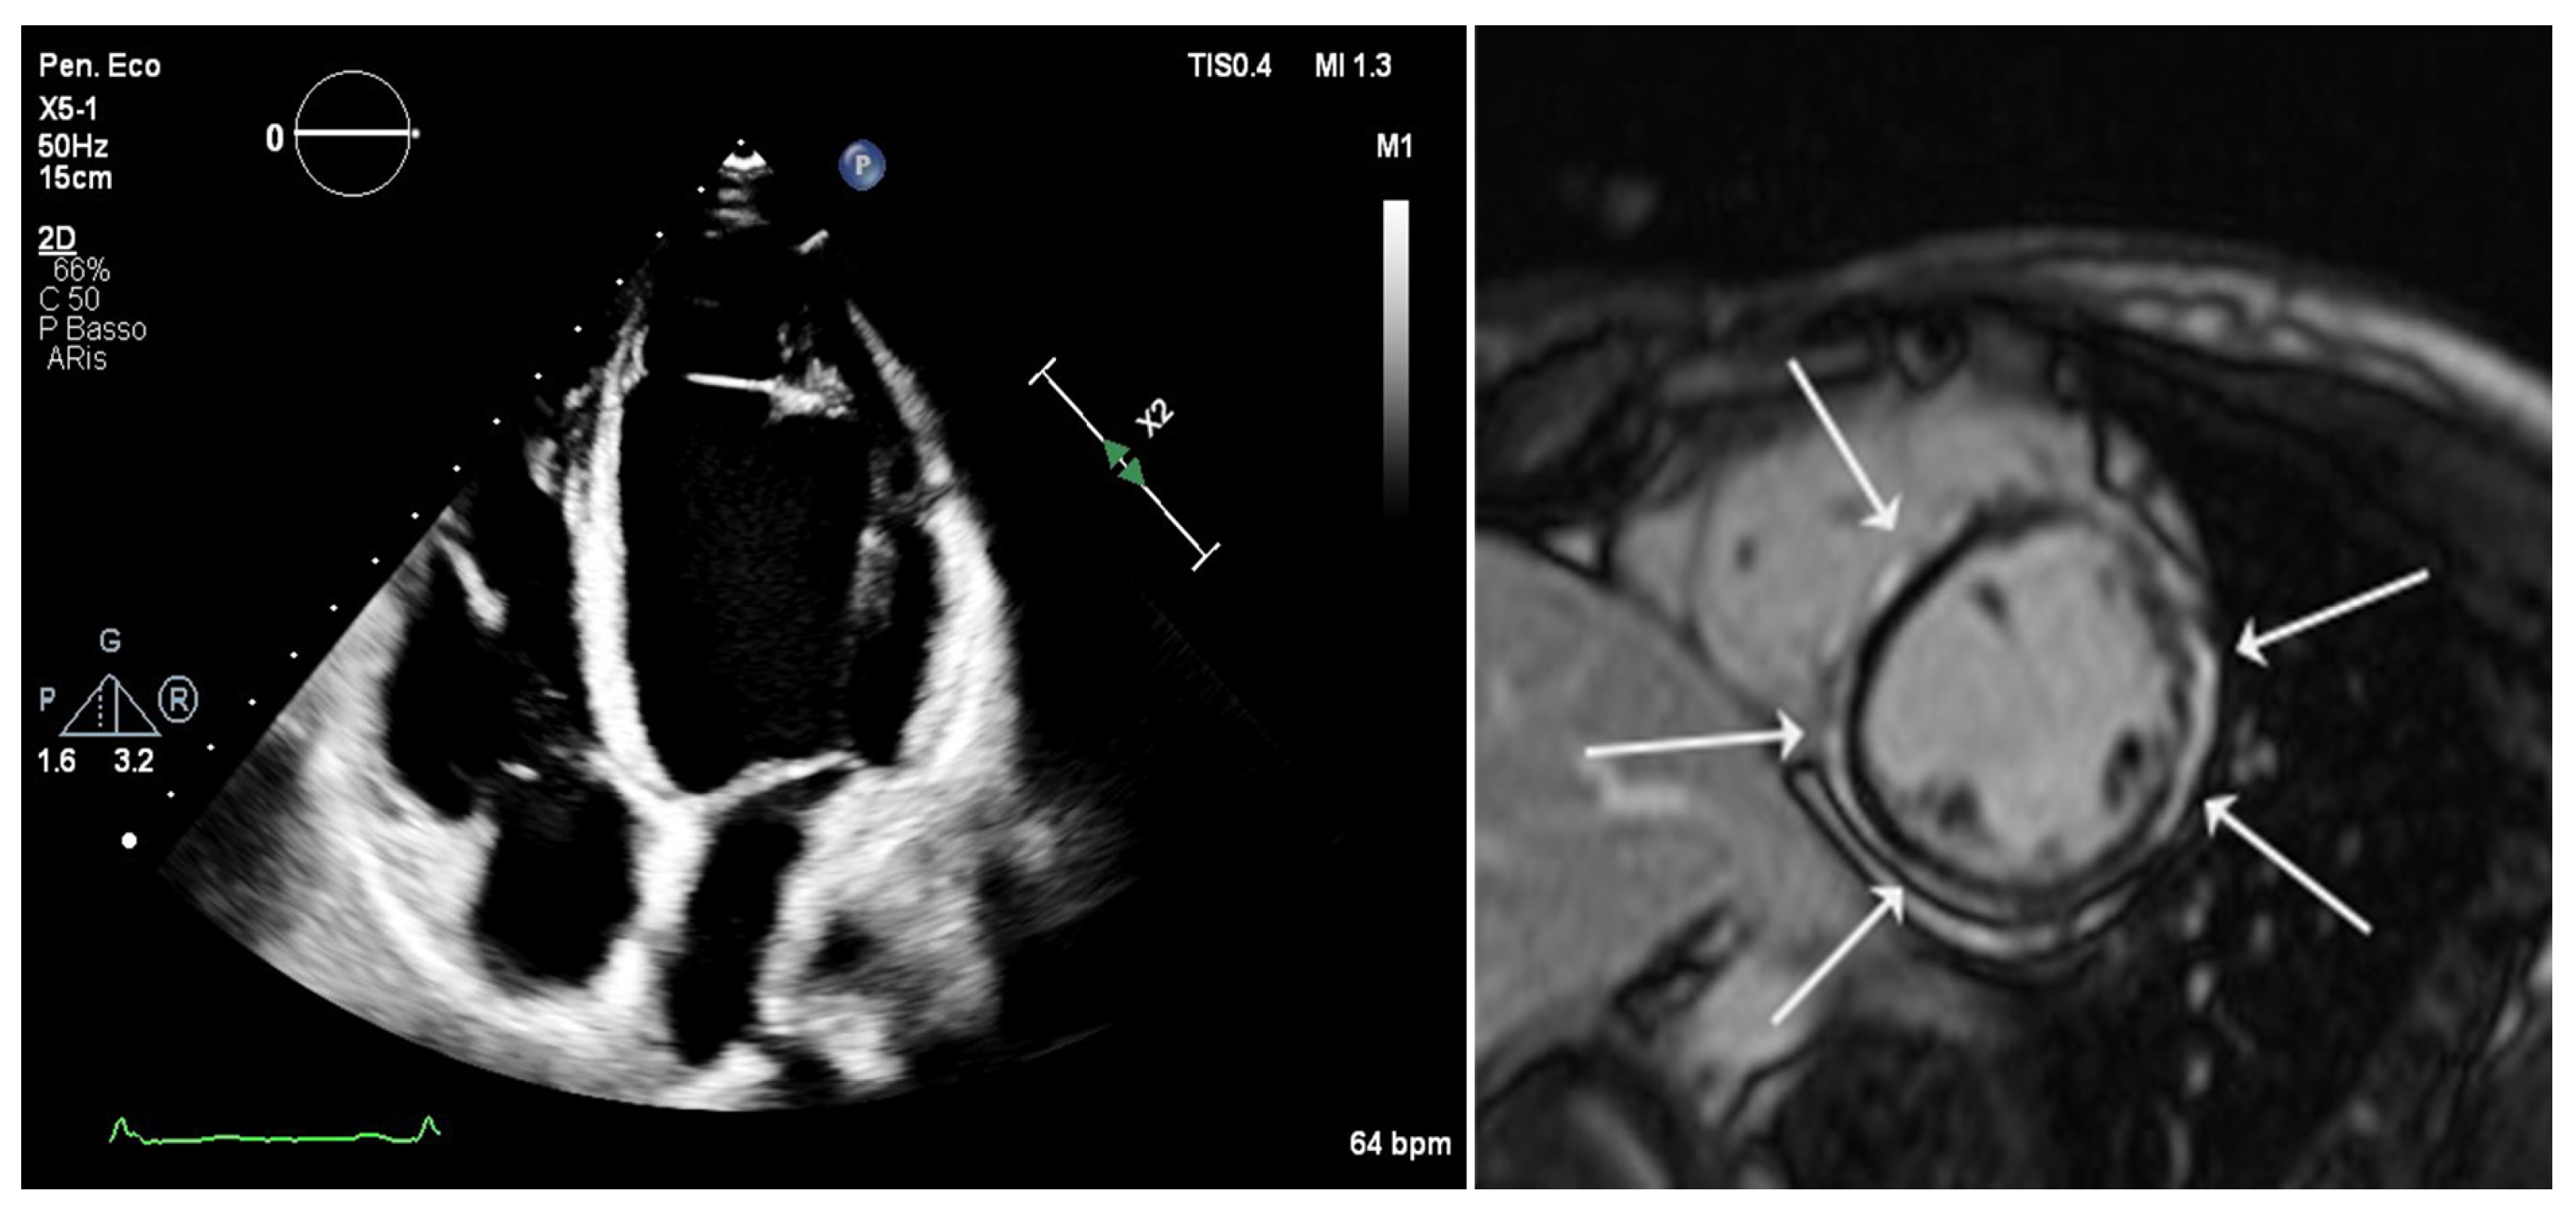

2. Current Diagnostic Criteria